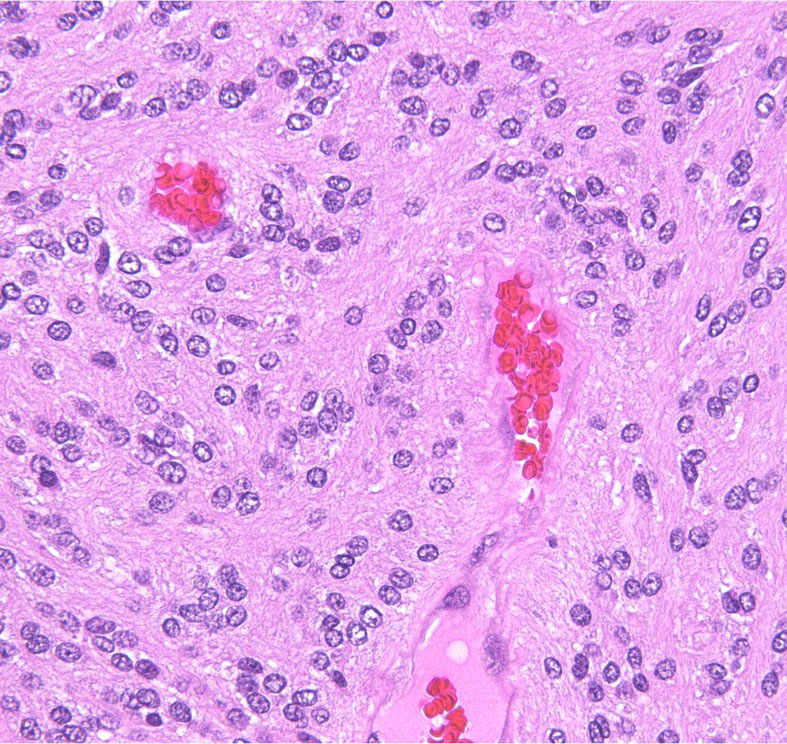

第4脳室床に発生した典型的な上衣腫 EPN-PFA の画像です。水頭症になって,頭痛と嘔吐,意識障害で発症しました。典型的なMRI画像と病理所見です。MRIでは第4脳室からマジャンディー孔を越えて脊髄背側まで長く腫瘍が伸びています。腫瘍内部に小さなのう胞が複数みられます。病理像では,血管周囲に細胞核がない無核野が認められます。血管周囲に伸びた繊細な単極性突起が集まった領域です。これは,血管周囲偽ロゼット perivascular pseudorosette という上衣腫に特徴的な病理所見です。

摘出した標本のHE染色です。左側ではperivascular pseudorosette(血管周囲の無核野)がみられ,右側ではependymal tube (ependymal canal) が認められます。

グレード2の組織像です。血管周囲に無核野があり,腫瘍の核は血管から離れているパターンが特長です。perivascular pseudo-rosetteといいます。